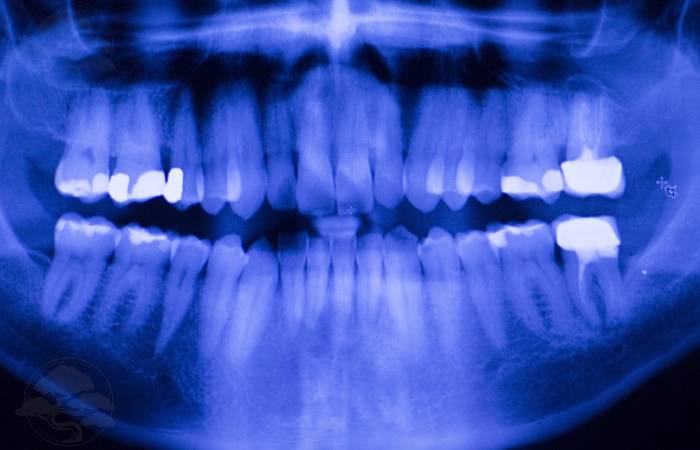

A filling is used to treat a small hole, or cavity, in a tooth.

Your dentist will remove the decayed tooth tissue and then fills the space with a filling material which sets in place.

There are several types of materials we use for our dental fillings in Liverpool, including:

- Amalgam – Silver-coloured and durable.

- Composite resin – Tooth-coloured and aesthetically pleasing.

- Gold – Long-lasting but more expensive.

- Porcelain – tooth coloured and resistant to staining.